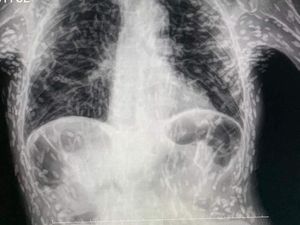

Seorang dokter asal Brazil membagikan gambar hasil sinar-X. Gambar itu memperlihatkan pasien memiliki kista sebagai hasil dari sisa infeksi larva cacing pita.